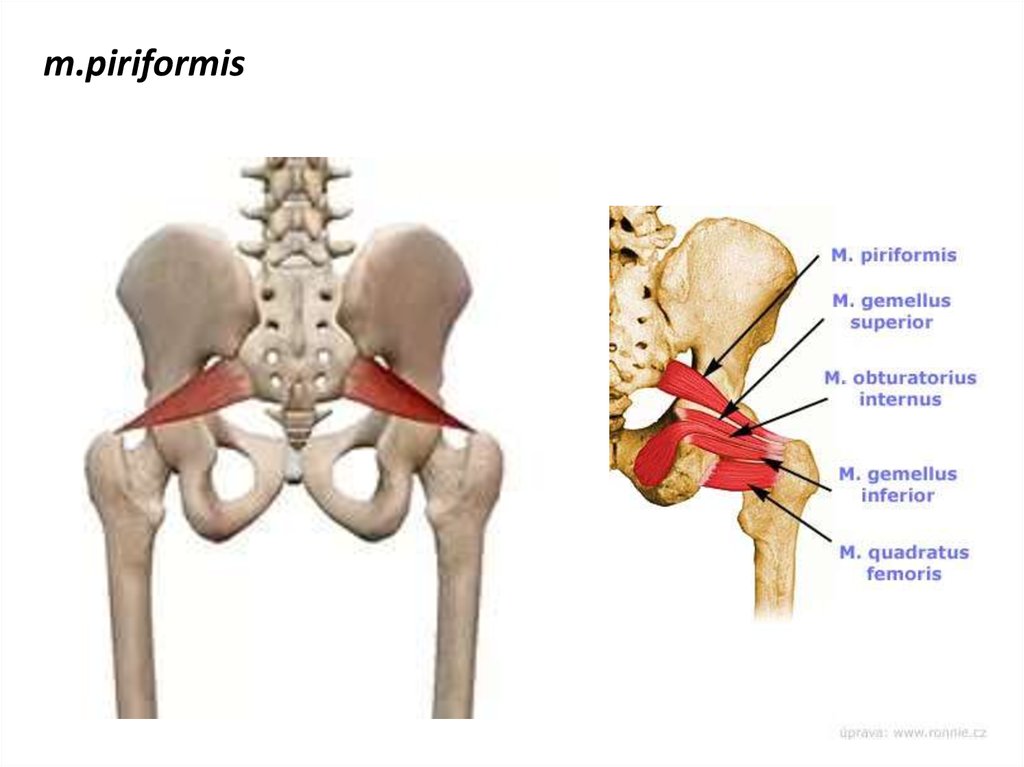

Анатомия мышц: Пириформис

:background_color(FFFFFF):format(jpeg)/images/article/die-hintere-hueftmuskulatur/G5mIfxL7N0ozMPCfEVmg_M._piriformis.png)